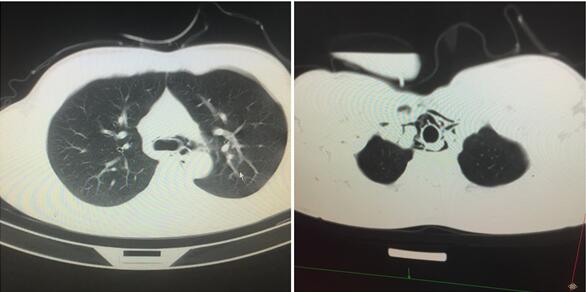

我们给患者急查胸部CT,上中纵膈内可见较多气体影聚集(如图1所示)。双肺未见肺主质病变,两肺门结构正常,气管及主气管大分支通畅。

图1 患者胸部CT影像

邀请胸外科急会诊,患者胸痛因纵膈气肿导致,原因考虑食管自发性破裂可能性大,立即收住胸外科继续治疗。

根据病情严重程度,可选择保守治疗和外科手术治疗。回过头我整理病史和症状,结合胸部CT也证实右纵膈积气,患者诊断较为明确。入住胸外科后,予以禁食、插胃管胃肠减压、加强营养等对症支持治疗,回访病人恢复良好。